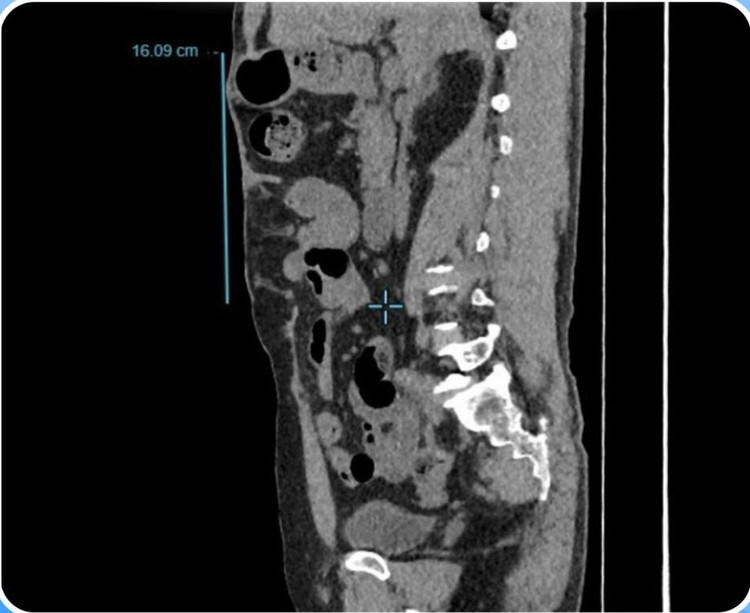

Qua thăm khám lâm sàng và chụp CT bụng, kết quả ghi nhận bệnh nhân có một khối thoát vị lớn ở thành bụng với đường kính hơn 16 cm.

Khối thoát vị thành bụng trên phim chụp của bệnh nhân - Ảnh BVCC